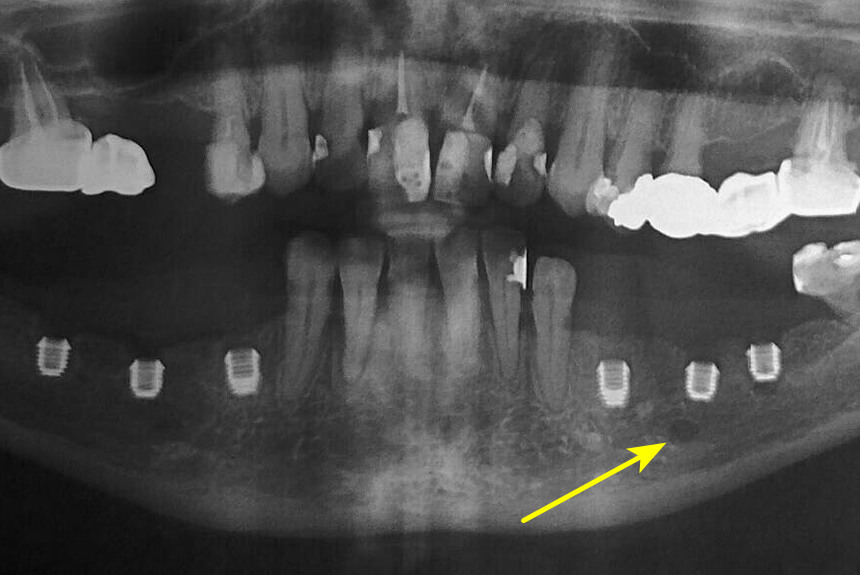

Short implants are an excellent and increasingly popular alternative for managing cases of moderate bone atrophy, primarily in terms of height. Unlike the techniques we mentioned before (zygomatic, transnasal, pterigoyd, subperiosteal), which resolve severe or extreme atrophy, short implants are a less invasive solution for when bone height is limited but still sufficient to anchor an implant of shorter length. Generally, an implant measuring 8 mm or less in length is considered “short.”

- In the upper jaw (posterior area): To avoid perforating the floor of the maxillary sinus. It is the direct alternative to "sinus lift" surgery.

- In the mandible (posterior area): To avoid damaging the inferior alveolar nerve, which could cause paresthesia (permanent or temporary numbness of the lip and chin).